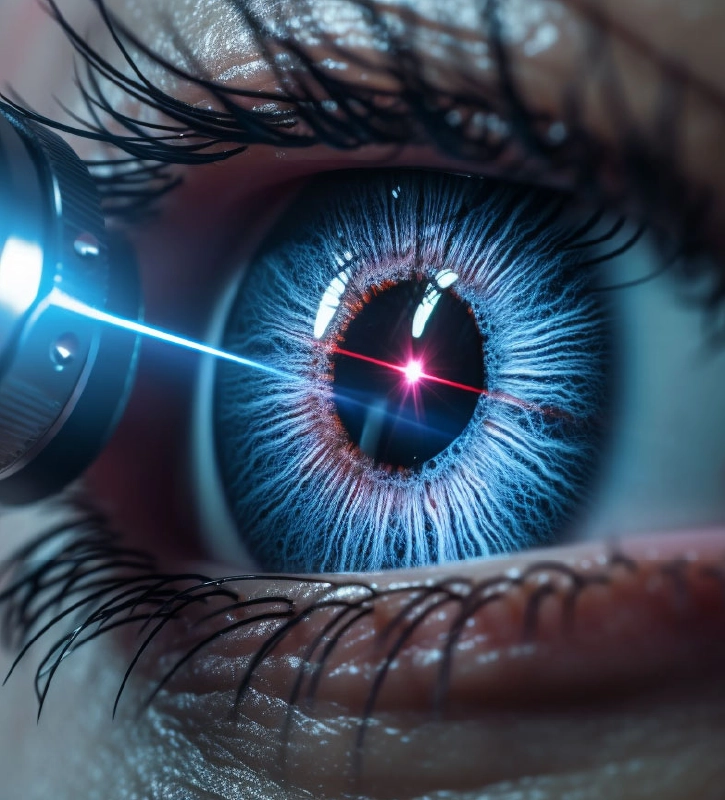

LÁSER DE RETINA

LÁSER DE RETINA

Láser de última generación para tratar agujeros y desgarros de retina, retinopatía diabética, oclusiones vasculares retinianas, entre otras.